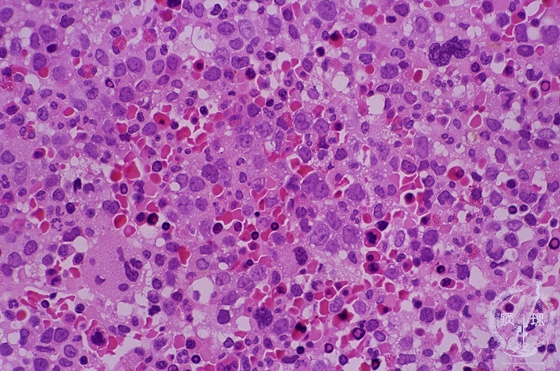

- 1.Bone marrow / Hematopoietic system

- (2)Megaloblastic anemia

Microscopic image (H&E high power view): Although an anemia is found in the peripheral blood, bone marrow shows marked hypercellularity with increased erythroblasts forming small aggregates. Megaloblasts have a relatively fine chromatin and the marked nucleoli (arrows). This type of anemia occurs due to the exhaustion of Vitamin B12 or folic acid by insufficient intake, malabsorption and/or excessive consumption.

Click the image to see the enlarged image.